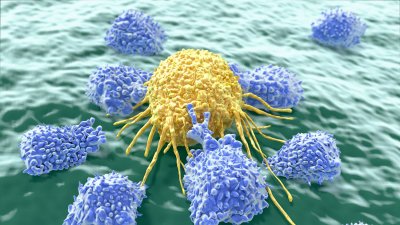

UCSF researchers have devised a CRISPR-based system called SLICE, which will allow scientists to rapidly assess the function of each and every gene in “primary” immune cells.

UCSF demonstrates that cancer is a clever engineer, capable of constructing entirely new disease-promoting networks out of raw materials readily available in the cell.